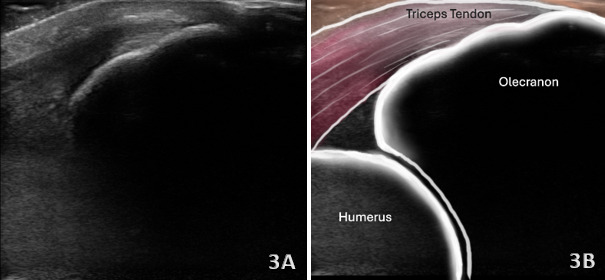

The triceps tendon is responsible for extension of the elbow during upper extremity functional activities that require the motion of pushing. Accurate diagnosis of tendon partial tears or ruptures is essential for appropriate treatment planning and optimizing patient outcomes. Diagnostic musculoskeletal (MSK) ultrasound offers a portable, real-time, and cost-effective alternative that is gaining traction in rehabilitation and sports medicine settings. MSK ultrasound has emerged as a valuable, non-invasive imaging modality for evaluating triceps tendon injuries including partial and complete tears, tendinopathy, and calcifications of the triceps insertion onto the olecranon, and even avulsions from the olecranon. MSK ultrasound is adept at detecting changes in tendon tissue composition and integrity, including both tendinopathies and partial thickness tears. Furthermore, this manuscript will review the utility of MSK ultrasound in evaluating the triceps injury, including its anatomy, common injury patterns, sonographic techniques, and clinical implications for professional rehabilitation. Diagnosis of acute injury by physical examination is often challenging and is frequently misdiagnosed. By integrating MSK ultrasound into clinical practice, providers can improve the accuracy of diagnosis, enhance diagnostic confidence, monitor healing progression, and guide rehabilitation strategies to optimal patient outcomes.